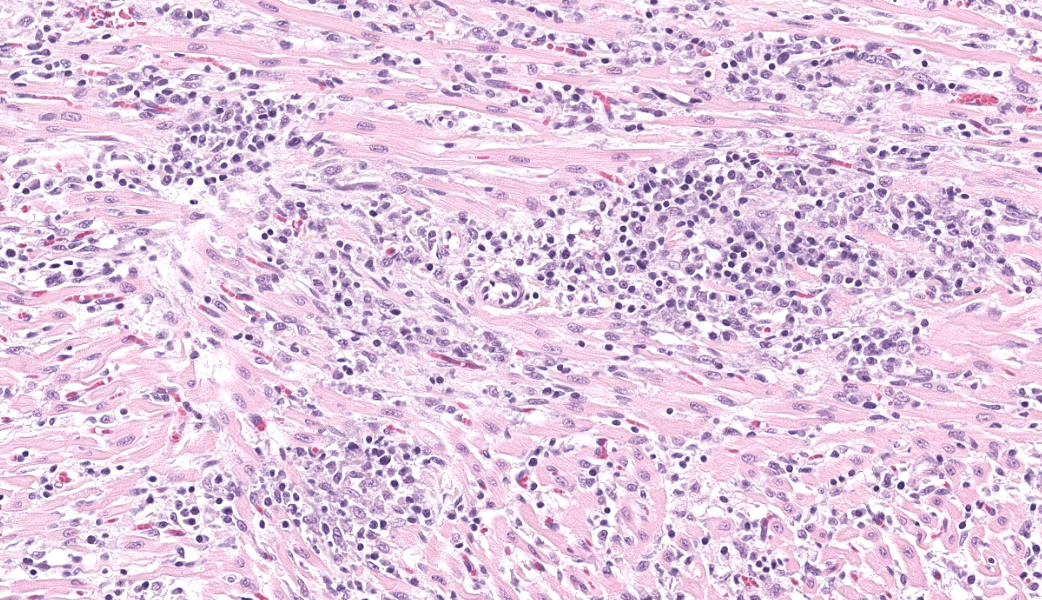

Expanding and infiltrating all layers of the heart, with the greatest severity in the myocardium, are large numbers of plasma cells, lymphocytes, and macrophages. Cardiomyocytes in areas of inflammation are multifocally hypereosinophilic, shrunken, and have striation loss with fragmented to absent nuclei (necrosis). There is mild, multifocal, interstitial fibrosis often associated with cardiomyocyte degeneration and inflammation. Throughout the myocardium, there are occasional cardiomyocytes that contain intrasarcoplasmic, variably sized (up to 100 μm in length) pseudocysts with numerous, 2-3 μm, round protozoal amastigotes.Contributor's Morphologic Diagnoses:

Heart: Severe, multifocal, chronic-active, lymphoplasmacytic and histiocytic pancarditis with intrasarcoplasmic pseudocysts containing amastigotesContributor's Comment:

T. cruzi can infect myocytes, endothelial cells, fibroblasts, and adipocytes, but has a tropism for cardiac muscle tissue.11 Grossly, there are no pathognomonic lesions for Chagas disease. Histologically, the cardiomyocytes will be expanded by a pseudocyst containing amastigotes. While best observed ultramicroscopically, the amastigotes will have a large nucleus and an adjacent rod-shaped kinetoplast, like Leishmania spp. Unlike the defined perpendicular orientation of the kinetoplast in Leishmania, the location of the kinetoplast relative to the nucleus changes during the life cycle and cannot be a diagnostic feature in Chagas disease.10 Unfortunately, additional diagnostics including PCR, culture, and serology were not performed so leishmaniasis cannot be completely ruled out, but the geographic and anatomic location of the organism along with the histologic appearance is most likely consistent with T. cruzi. Infection results in marked inflammation of the heart, often not associated with the intracellular pseudocysts. Myocarditis can lead to heart failure with cardiac arrest and potentially fatal arrhythmias. In this case, there was multi-organ evidence of heart failure including ascites (abdominal effusion) and centrilobular hepatocyte necrosis due to hypoxia.